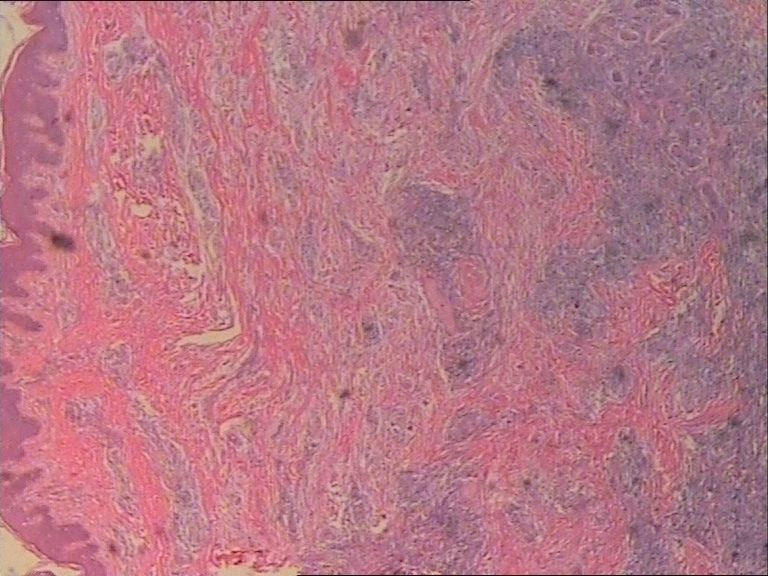

患者    女    47岁    腰部皮下肿块5x4cm,皮肤表面灰褐色,无隆起,无压痛。体格检查无其他异常。

最后诊断为Rosai-Dorfman病。

单核及多核组织细胞是本病不特异但恒定的特点,可惜高倍镜图片看不清核结构,显微镜下很清楚。

图片很清晰,挺好,就是看不明白,好像就是很多的多核巨细胞和炎细胞?似乎还有真菌菌丝似的东西?似乎是个肉芽肿病变,还得做活检手术吧?

是的,拿来给大家看的主要原因是本病细胞学比组织学特征更明显。